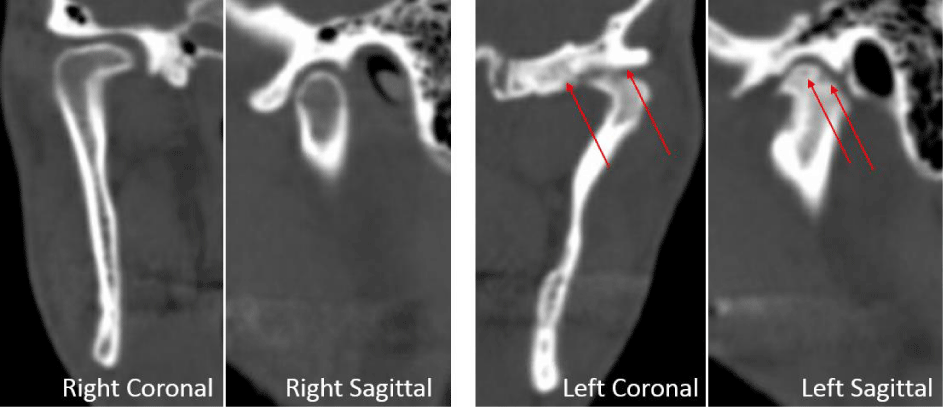

A 53-year-old male presented with a complicated musculoskeletal history consisting of head and neck dystonia and suprahyoid musculature spasms resulting in painful recurrent mandibular subluxation. Examination revealed a mouth-opening of 60 mm with ongoing subluxation due to muscle spasms. The CT scan of the left side suggested severe degenerative changes with multiple rounded erosive foci and a hazy periosteal reaction at the skull base (Figure 6). The T1 weighted MRI showed low signal intensity in the condylar bone marrow on the left. The disc was not visualized and there was no evidence of intra-articular mass (Figure 7). Diagnostic arthroscopy of the left showed a large central perforation of the disc with remarkable nodular synovitis. Synovial biopsy, synovectomy and debridement were performed (Figure 8). Histologic examination showed PVNS (Figure 9). Additional surgical treatment for the dislocation and the degenerative changes of the TMJ was deferred until further control of the muscular dystonia was achieved.